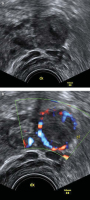

Tipps und Tricks im Gyn-Ultraschall: Sonographische Kennzeichen des Corpus luteum

Journal für Gynäkologische Endokrinologie 2013; 7 (4) (Ausgabe für Österreich): 24-26 Journal für Gynäkologische Endokrinologie 2013; 7 (4) (Ausgabe für Schweiz): 28-30 Volltext (PDF) Abbildungen